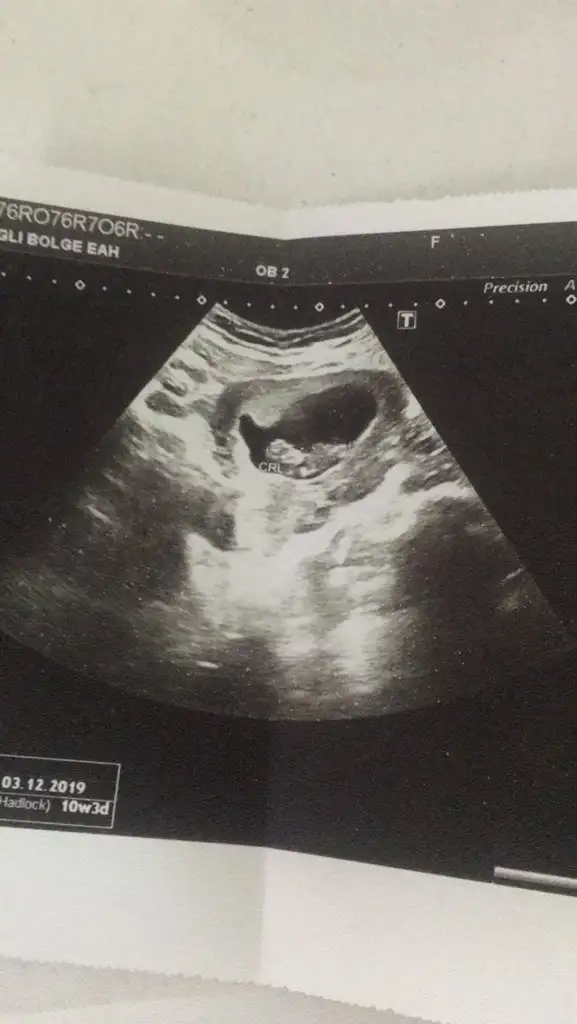

Bu dogrumu canm benim 7 haftalik teoriye solda karinda erkek zaten gissedyrdm dr birgun onceerkek ikili testte kiz dedi anlamadk 14 haftalgm ins degsr9+4 göre erken sekil almış erkek diyorum

Yok tek 14 haftalik var iste cnm ama 7. hqftalikta ultrason kagidana gore erkek net belli yarn atarm erkek hissedyrm hep icimde ama anlamadm10 yada 11